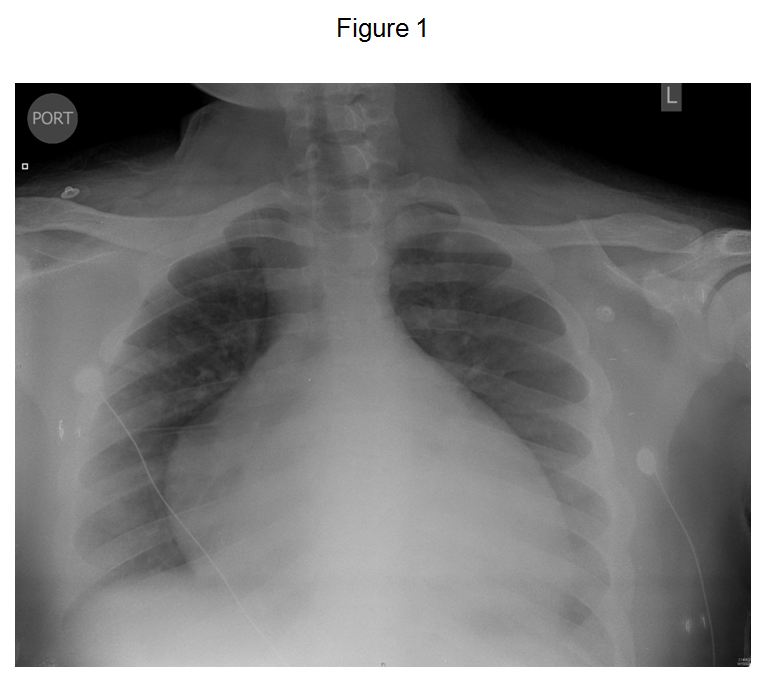

A 16 year old obese boy with a BMI of 45 kg/m2 presented to the emergency department for the first time with hemoptysis and shortness of breath lasting for one week. His admission chest x-ray is shown in Figure 1.

He was diagnosed as having idiopathic dilated cardiomyopathy and was in congestive heart failure (CHF). His ejection fraction was 18%. During the admission he was noted to have occasional apneas during sleep. His sleep history revealed snoring, but no gasping episodes or excessive daytime somnolence. A representative 2-minute epoch from the polysomnogram (PSG) is presented in Figure 2.